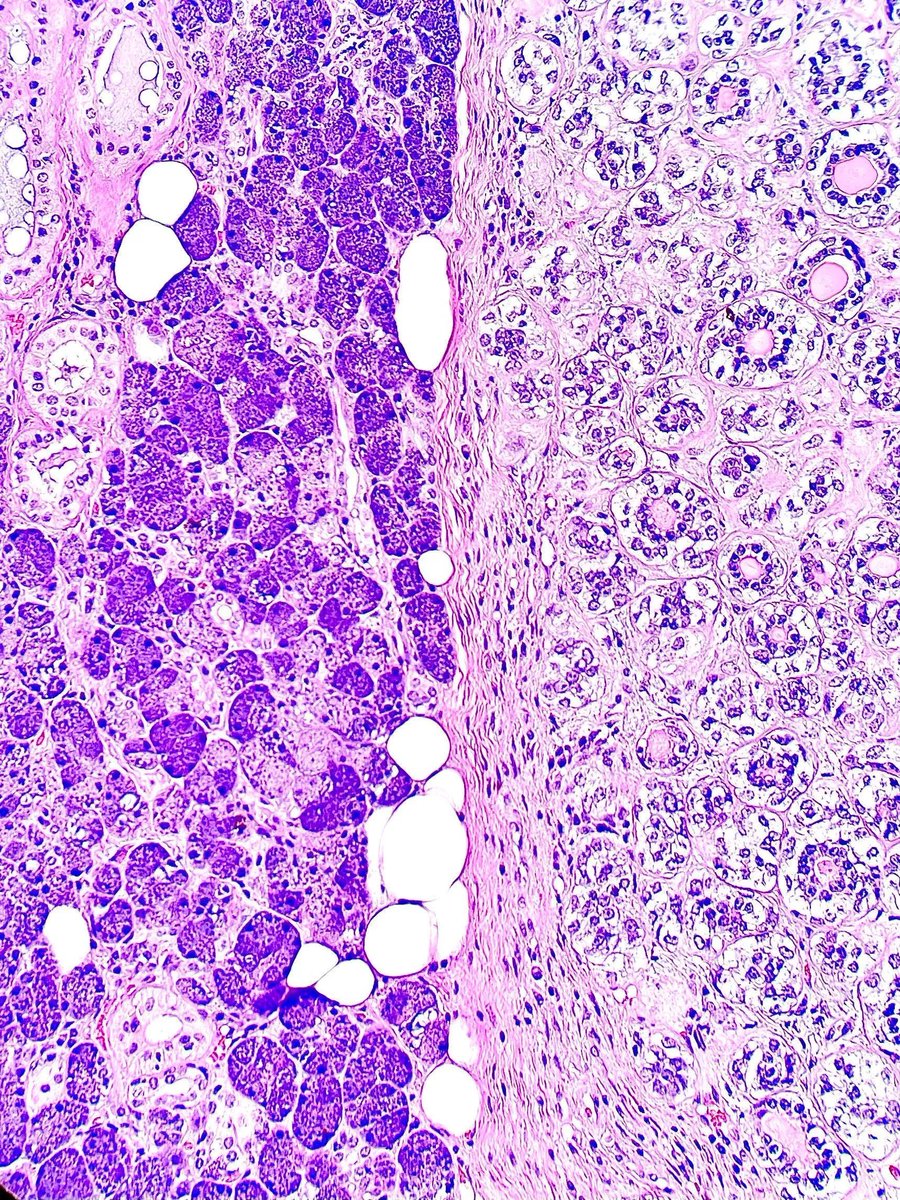

Researchers long believed they knew the answer to these questions: that immune cells mature through a process called central immune tolerance (see image). However, our immune system turned out to be more complex than they believed. Mary Brunkow, Fred Ramsdell and Shimon Sakaguchi have been awarded the 2025 Nobel Prize in Physiology or Medicine for their discoveries concerning peripheral immune tolerance.